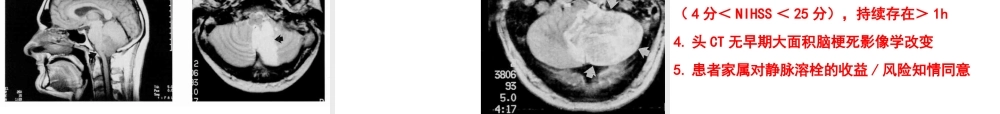

1急性脑梗塞及溶栓治疗单晓琳内分泌一科还能溶栓吗?•溶栓安全吗?•应该溶栓吗?•使用什么药物溶栓?•药物剂量如何?•如何临床管理?•如何监测?如何护理?•如果不进行溶栓治疗会怎样?脑血栓形成的病理生理学•缺血半暗带的形成、演变和临床意义急性脑梗死病灶是由中心坏死区及其周围的缺血半暗带(ischemicPenumbra)组成。急性脑梗死发生后,在中心坏死区的周围形成缺血半暗带。缺血半暗带内仍有侧支循环存在,可获得部分血液供给,尚有大量可存活的神经元。如果血流迅速恢复,损伤是可逆的,脑代谢障碍可恢复,神经细胞仍可存活并恢复功能。保护缺血半暗带区的神经元是急性脑梗死治疗成功的关键。早期再灌注治疗是缺血性脑卒中救治的关键早期再灌注治疗是缺血性脑卒中救治的关键必须分秒必争必须分秒必争缺血半暗带(可逆性脑损伤)GonzálezRG.AJNRAmJNeuroradiol.2006Apr;27(4):728-35.SaverJF.Stroke2006;37:263-266.未治疗的缺血性脑卒中患者,缺血区每分钟将有190万个神经元死亡10早期溶栓再灌注治疗,有利于挽救可逆性脑损伤9缺血中心区(不可逆性脑损伤)缺血性卒中治疗现状•静脉溶栓•动脉溶栓•动静脉联合溶栓•机械溶栓溶栓治疗的时间窗•前循环静脉内溶栓的时间窗为3小时动脉内溶栓的时间窗为6小时•后循环静脉或动脉的溶栓时间窗可达12小时缺血性卒中的初步诊断发病时间发病时间:是患者最后看起来正常状态的时候为发病时间,而不是症状出现时间7异常灌注的区域可以是坏死组织或存在坏死风险的组织结合弥散及灌注影像可以帮助我们确认那些存在坏死风险的组织,亦即所谓的缺血半影区在左侧首先一个DWI显示一个不可逆的坏死中间图像显示灌注不足的范围更大右侧是弥散-灌注的结合像蓝色显示缺血半影区,这些组织是可以通过治疗获得恢复的Diffusioninyellow.Perfusioninred.Mismatchinblueispenumbra.发病一小时后行MR扫描,你发现了什么?DWI序列上显示一个右侧大脑中动脉供血区的广泛的弥散受阻基底节同时受累弥散成像病变范围与DWI一致,说明病变属于坏死组织,溶栓治疗是不需要的另一个大脑中动脉梗死。CT上清楚的显示低密度区(即:不可逆坏死)DWI与灌注与其范围一致,所以溶栓治疗是不需要的另一病人的DWI,下面看弥散成像弥散显示病变范围与DWI完全不匹配几乎整个左侧大脑半球都出现灌注不足,也即是atrisk(有坏死的风险)中这个病人是一个理想的溶栓治疗对象后循环缺血的危险因素不可调...